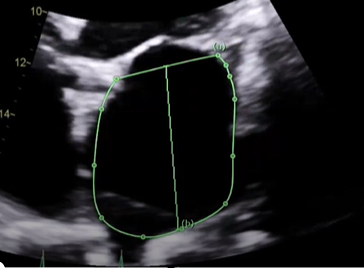

what measure measurement is this, explain how would want to measure this and what View,

Measured the LA area and length in A4C, at its largest dimension before the leaflet tips (MV) open at end-systole, want to exclude the Pulmonary vein and mitral annulus, this is when you need to trace the chamber and length. the normal LA area is going to be less than or equal to 20 or 24? (THIS IS NOT OUT LAV INDEX)